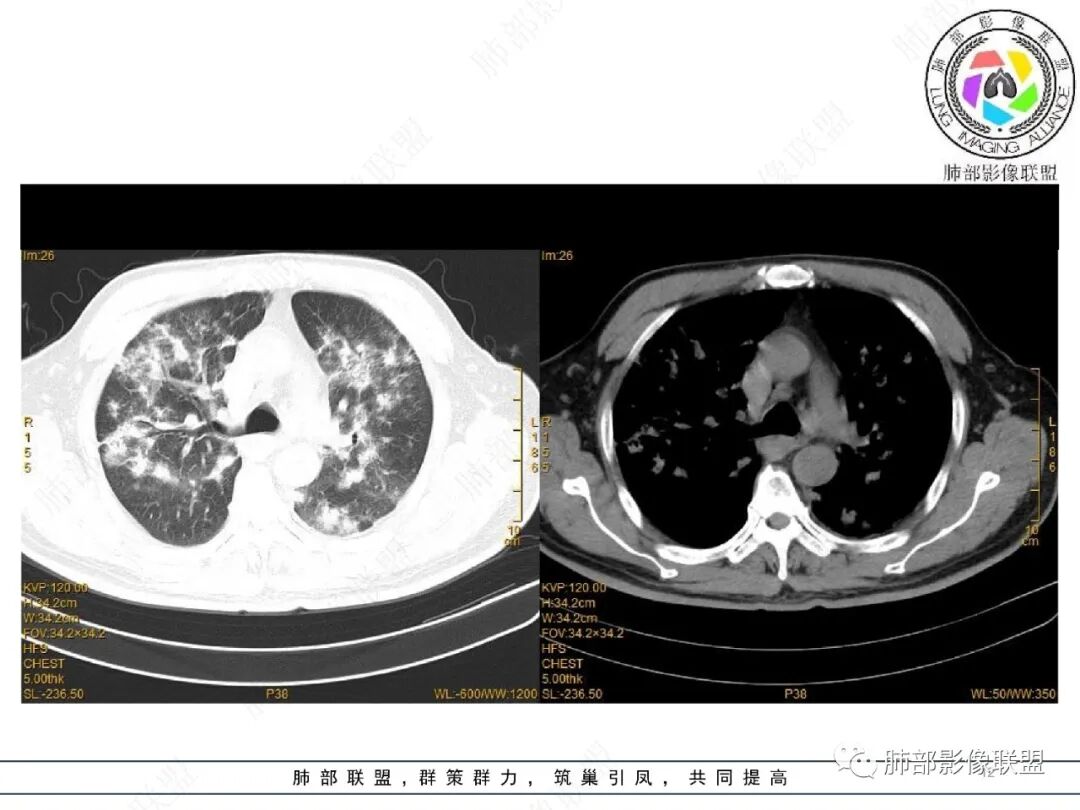

2022.2.17CT显示两肺中内带多发结节影、斑片影、条索影,部分病灶侧向融合与胸膜平行。部分病灶沿着支气管血管束分布、其内支气管稍扩张。部分病灶呈反晕征。大部分病灶边界显示清晰,部分病灶周围可见边界不清的GGO。2022.4.12CT显示两肺中内带多发结节影、条索状、条带状高密度影,边界收缩平直凹陷,大部分病灶沿着支气管血管束分布,亦有位于胸膜下侧向融合与胸膜平行的病灶。总体与第一次CT对比两肺病灶明显吸收。